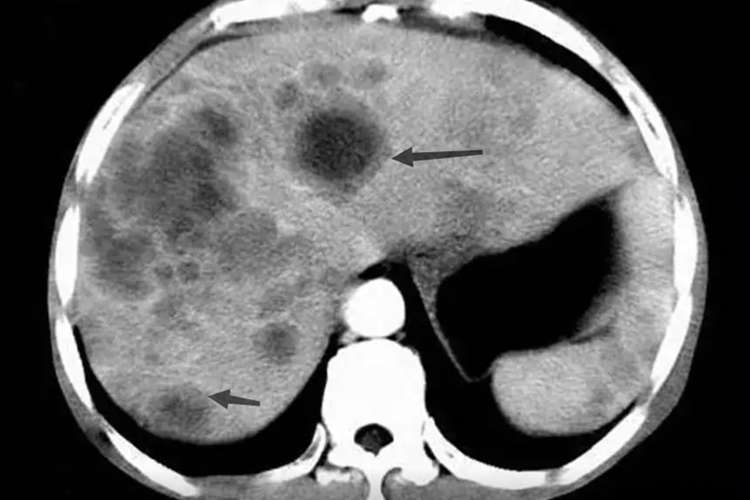

转移性肝癌患者进行影像学检查肝内有牛眼征表现,即肝内出现多发结节,其边界清楚,周缘区低回声晕环,内部为高回声,有时高回声的中央有小片状低回声或无回声区。结节较小者肝大小可正常,较大转移灶可引起肝局部肿大,挤压肝内血管会出现移位等征象。

肝是多种恶性肿瘤中最易发生转移的器官。其他器官的恶性肿瘤也可通过血液、淋巴或直接侵犯等途径转移到肝,称转移性肝癌。转移性肝癌会出现大小不一,数目不等的小结节,多数散在分布于肝内,结节中央易发生坏死,影像可见肝内回声不均匀,进而有牛眼征表现。